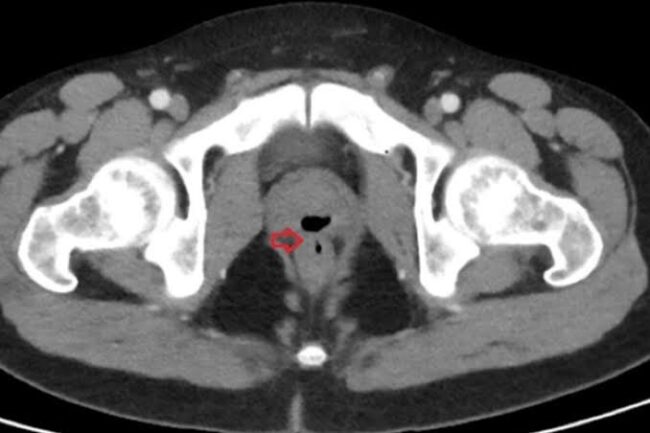

Após ficar em coma durante três semanas depois de uma intoxicação causada por cocaína e fenciclidina (PCP), um homem passou a sofrer uma série de complicações envolvendo o pênis e o ânus. De acordo com o jornal Daily Star, ele chegou a fazer cocô pelo órgão genital e ejaculou pelo reto. O homem de 33…